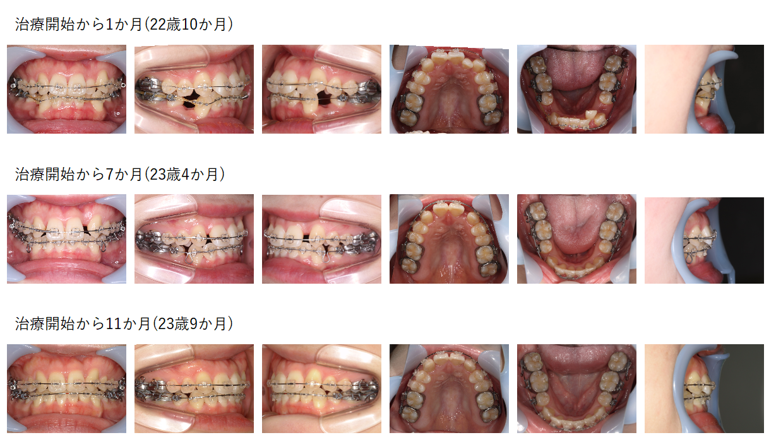

【治療例】初診時年齢:22歳7か月 / 性別:女性 / 主訴:ガタガタ、噛み合わせ、前歯が大きい

主訴:ガタガタ、噛み合わせ、前歯が大きい

診断名:上顎V字歯列弓を呈する叢生

使用した主な装置:急速拡大装置、バイヘリックス装置、マルチブラケット装置、顎間ゴム

抜歯/非抜歯および抜歯部位:非抜歯

治療期間:3年8か月 (2021年9月~は保定期間)

治療回数:27回

リスクの副作用:歯の移動や抜歯による違和感や疼痛、口内炎、歯肉退縮、歯根吸収が生じることがある